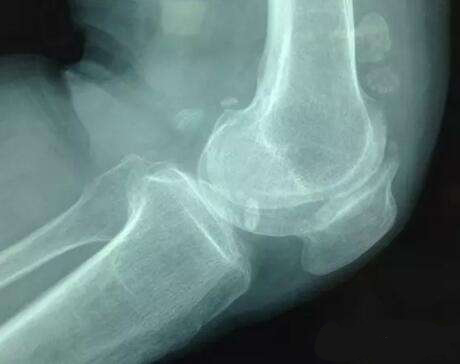

不少人到了40岁以后,就会察觉到一个明显的变化,腿脚没有以前灵便,甚至膝盖痛。这是怎么回事呢?40岁以后中老年人膝关节肿痛,最主要的原因就是膝关节骨关节炎。为什么膝骨关节炎会在这个年龄段频频发难呢?一切要从软骨说起……

但关节用的久了,关节软骨也会老化,组织结构会变稀疏,水分也会减少,久而久之软骨产生磨损、遭到破坏,这层关节中的“缓冲垫”损毁到一定程度,处于软骨保护下的骨端就会直接摩擦,就会造成骨质增生、骨刺形成,甚至畸形出现。

增生的骨刺压迫到周围组织、神经、血管,会产生疼痛,被磨损脱落的软骨碎屑夹在关节中间,会引发炎症,使关节产生肿、热、痛,就意味着膝骨关节炎已经发生。